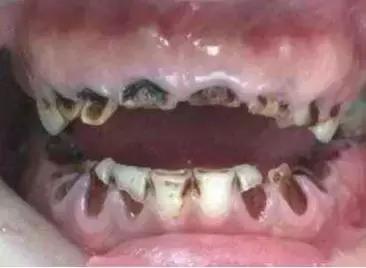

一颗蛀牙让7岁男孩的脸烂穿

据青年时报报道, 一个7岁的男孩面部下颌骨的位置长了个大脓包,脓包处的皮肤不断渗着脓液。皮肤科医生始终无法确定病灶,于是请来牙医参与会诊。最后发现孩子的“六龄牙”不仅被“蛀”了,还发生了慢性炎症。

“一般情况下,儿童到了6周岁时,在牙列最后方最先萌出的牙就是六龄牙,六龄牙也是人的第一颗恒牙。儿童蛀牙中发病率最高的为窝沟蛀牙,约占儿童蛀牙的80%,而六龄牙就是窝沟蛀牙的好发部位。”

牙医说,“这个小患者的六龄牙被蛀后发生了炎症,炎性分泌物沿着下颌骨侵蚀,导致下颌骨、黏膜、皮肤一层层被烂穿,就像老鼠打洞一样,最终在面部皮肤被发现脓包。”